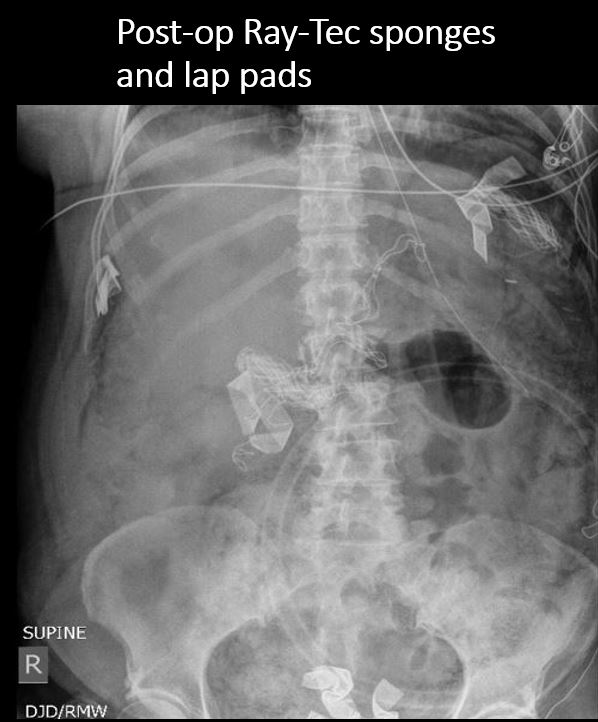

There are surgical drains or other post-surgical changes. |

Yes | NA |